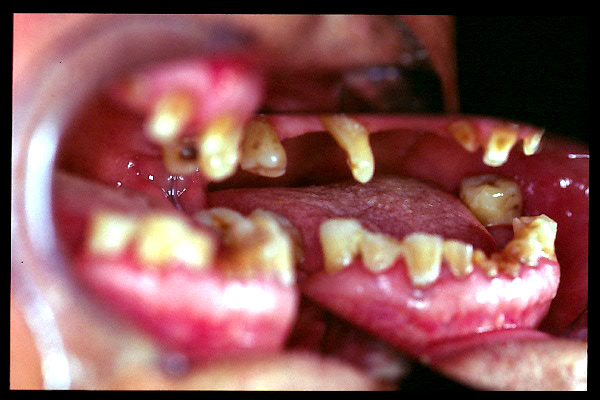

CM Edentulismo parcial, restos radiculares, caries y placa bacteriana